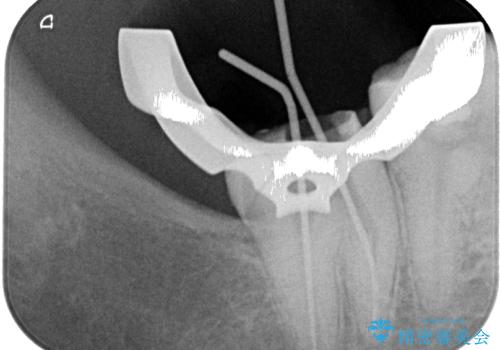

最後の確認方法として、局所麻酔を行わずに最後臼歯の銀歯を外し、神経組織近くまで歯質を切削したところ痛みなどを全く感じず、その後無菌的環境下にて切削を進めたところ、神経組織の一部が壊死していることが確認されました。

その後は速やかに根管治療を行い、初回の処置以降は痛みや違和感が一気に引いたため、根管治療後にオールセラミッククラウンにて補綴治療を行うこととしました。